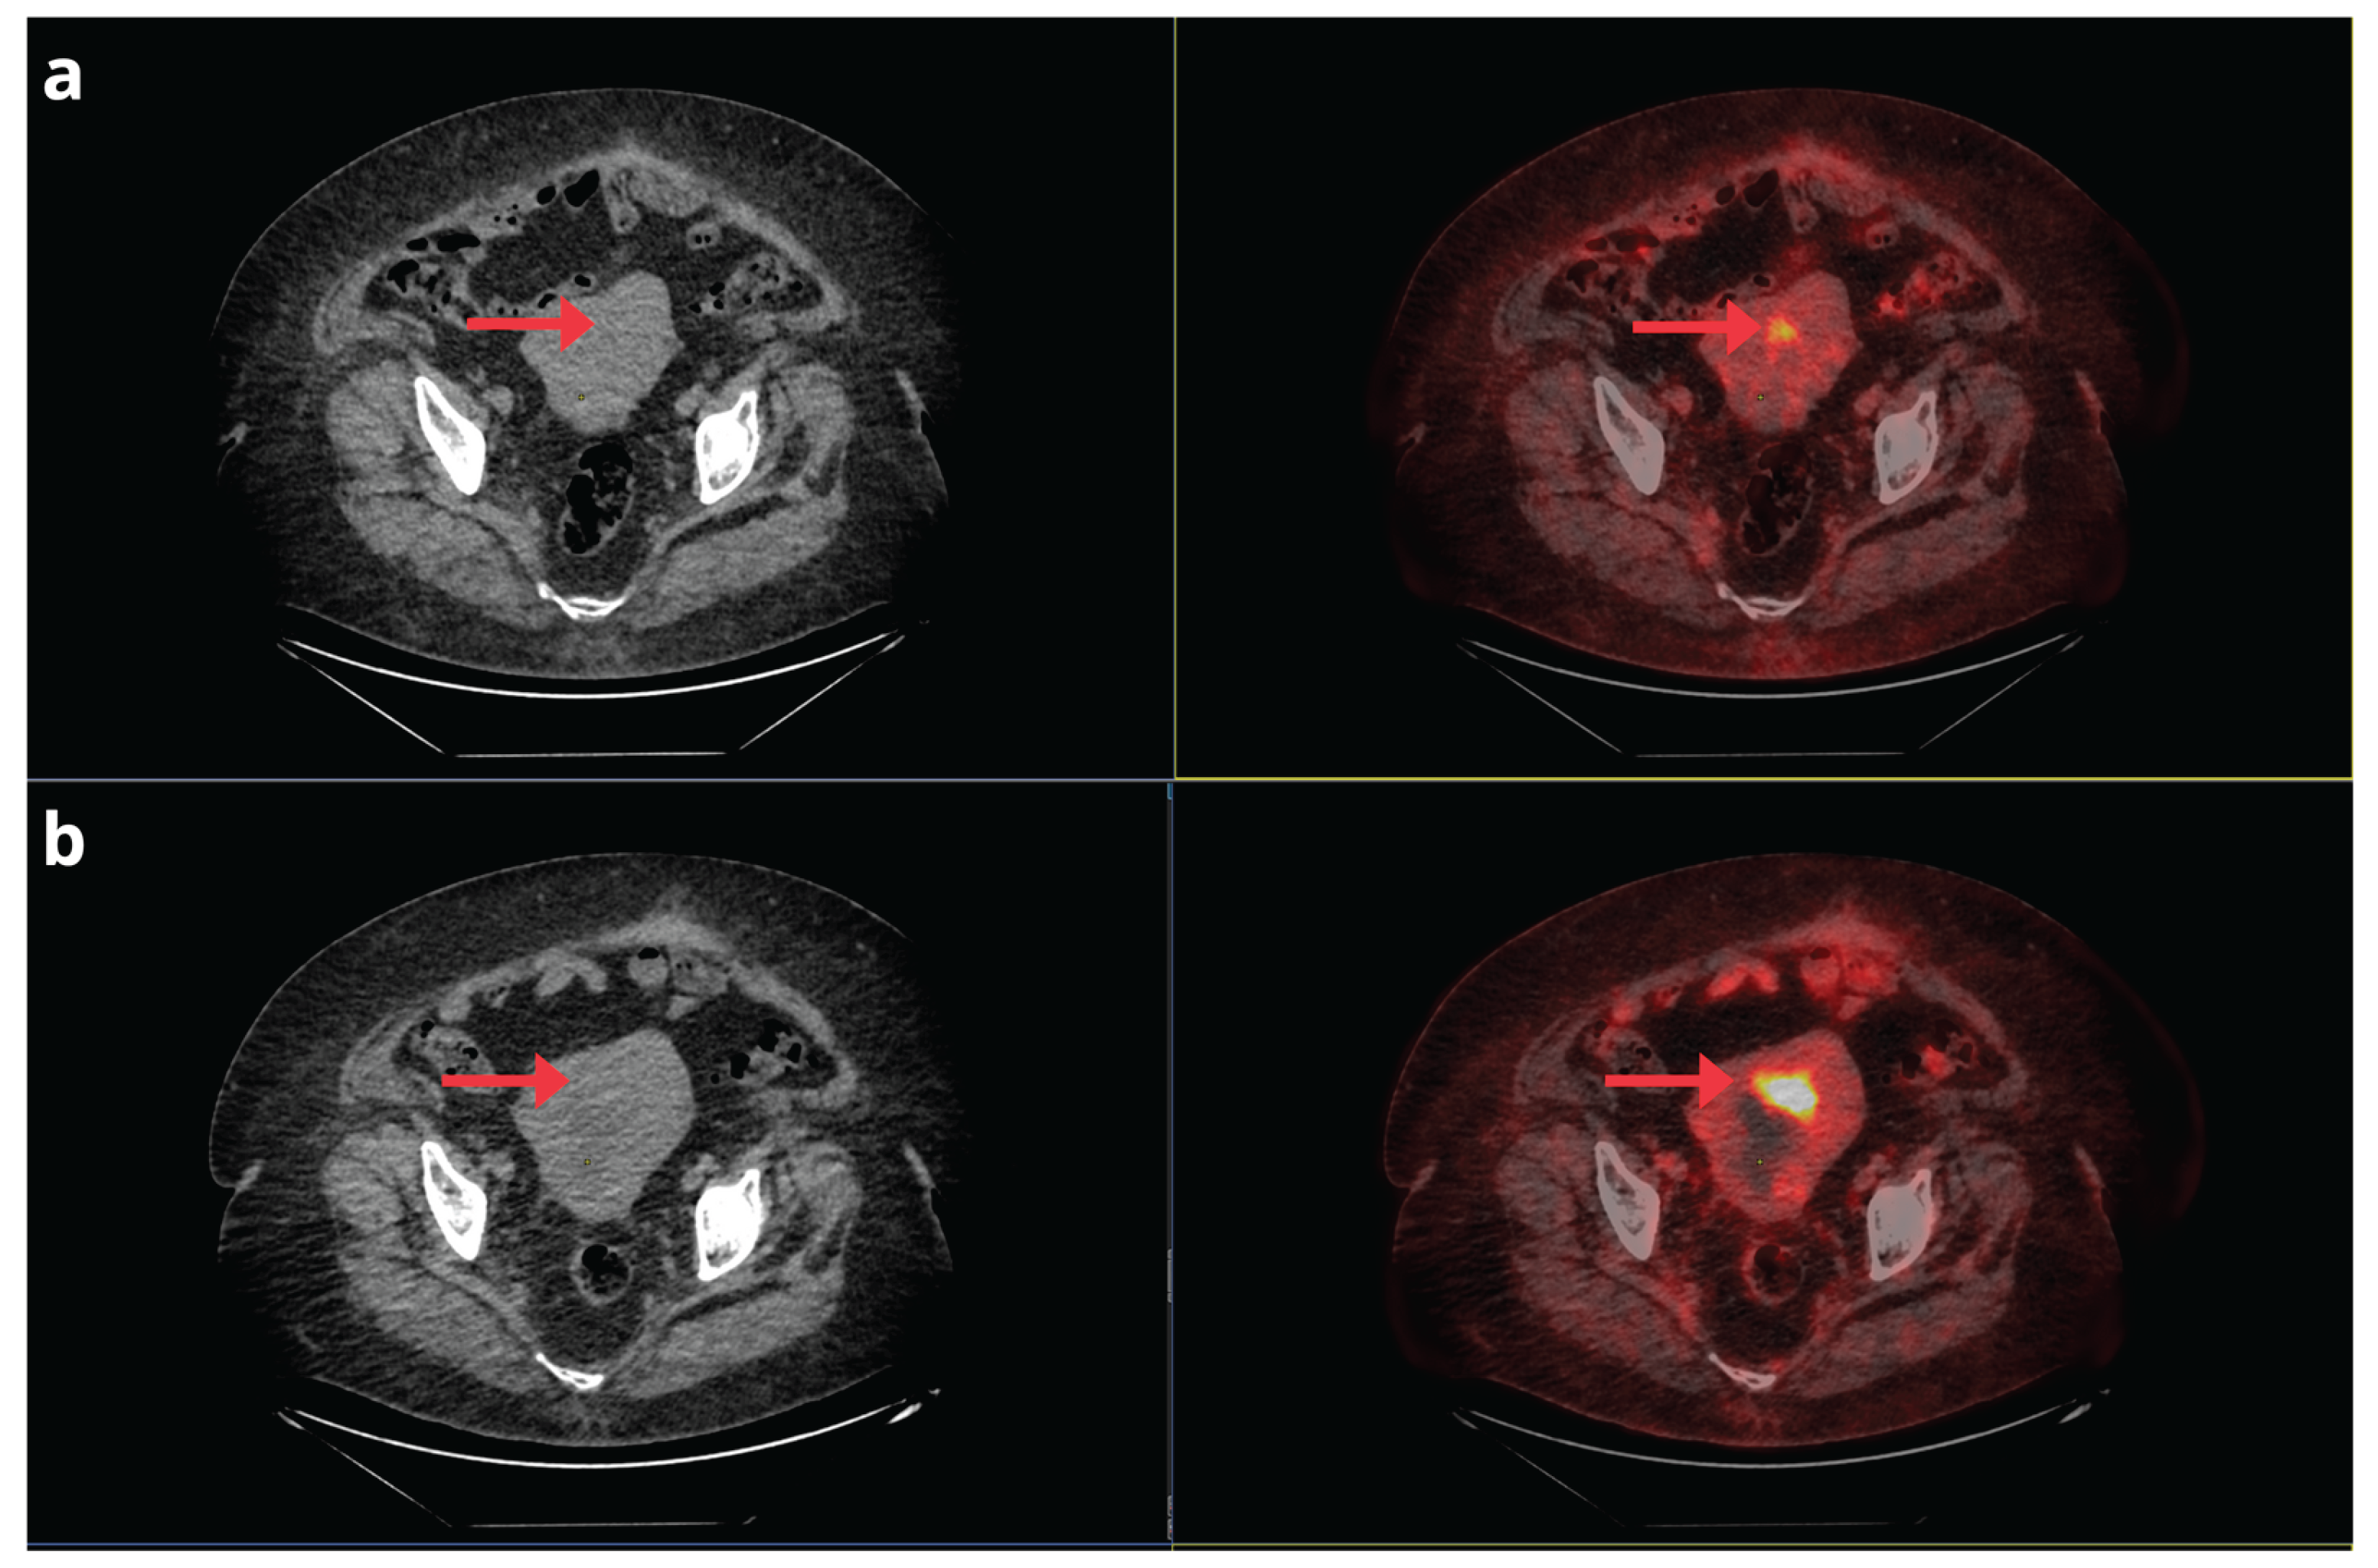

- Bian, L.; Wang, M.; Gong, J.; Liu, H.; Wang, N.; Wen, N.; Fan, W.; Xu, B.; Wang, M.; Ye, M.; et al. Comparison of Integrated PET/MRI with PET/CT in Evaluation of Endometrial Cancer: A Retrospective Analysis of 81 Cases. PeerJ 2019, 7, e7081. [CrossRef]

- Ironi, G.; Mapelli, P.; Bergamini, A.; Fallanca, F.; Candotti, G.; Gnasso, C.; Taccagni, G.L.; Sant’Angelo, M.; Scifo, P.; Bezzi, C.; et al. Hybrid PET/MRI in Staging Endometrial Cancer: Diagnostic and Predictive Value in a Prospective Cohort. Clin Nucl Med 2022, 47, e221–e229. [CrossRef]

- Yu, Y.; Zhang, L.; Sultana, B.; Wang, B.; Sun, H. Diagnostic Value of Integrated 18F-FDG PET/MRI for Staging of Endometrial Carcinoma: Comparison with PET/CT. BMC Cancer 2022, 22, 947. [CrossRef]

- Bezzi, C.; Zambella, E.; Ghezzo, S.; Fallanca, F.; Samanes Gajate, A.M.; Franchini, A.; Ironi, G.; Bergamini, A.; Monaco, L.; Evangelista, L.; et al. 18F-FDG PET/MRI in Endometrial Cancer: Systematic Review and Meta-Analysis. Clin Transl Imaging 2022, 10, 45–58. [CrossRef]

- Tsuyoshi, H.; Tsujikawa, T.; Yamada, S.; Okazawa, H.; Yoshida, Y. Diagnostic Value of 18F-FDG PET/MRI for Staging in Patients with Endometrial Cancer. Cancer Imaging 2020, 20, 75. [CrossRef]

- Nie, J.; Zhang, J.; Gao, J.; Guo, L.; Zhou, H.; Hu, Y.; Zhu, C.; Li, Q.; Ma, X. Diagnostic Role of 18F-FDG PET/MRI in Patients with Gynecological Malignancies of the Pelvis: A Systematic Review and Meta-Analysis. PLoS One 2017, 12, e0175401. [CrossRef]

- Kirchner, J.; Sawicki, L.M.; Suntharalingam, S.; Grueneisen, J.; Ruhlmann, V.; Aktas, B.; Deuschl, C.; Herrmann, K.; Antoch, G.; Forsting, M.; et al. Whole-Body Staging of Female Patients with Recurrent Pelvic Malignancies: Ultra-Fast 18F-FDG PET/MRI Compared to 18F-FDG PET/CT and CT. PLoS One 2017, 12, e0172553. [CrossRef]

- Zheng, M.; Xie, D.; Pan, C.; Xu, Y.; Yu, W. Diagnostic Value of 18F-FDG PET/MRI in Recurrent Pelvis Malignancies of Female Patients: A Systematic Review and Meta-Analysis. Nucl Med Commun 2018, 39, 479–485. [CrossRef]

- Sawicki, L.M.; Kirchner, J.; Grueneisen, J.; Ruhlmann, V.; Aktas, B.; Schaarschmidt, B.M.; Forsting, M.; Herrmann, K.; Antoch, G.; Umutlu, L. Comparison of 18F–FDG PET/MRI and MRI Alone for Whole-Body Staging and Potential Impact on Therapeutic Management of Women with Suspected Recurrent Pelvic Cancer: A Follow-up Study. Eur J Nucl Med Mol Imaging 2018, 45, 622–629. [CrossRef]